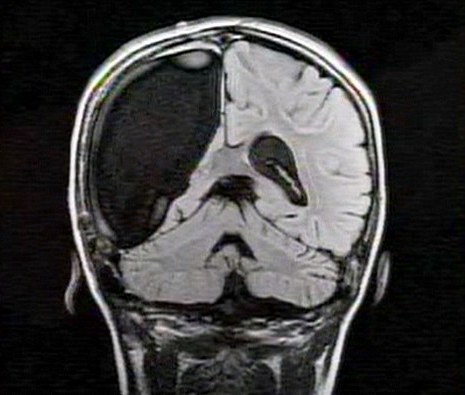

卡梅倫莫特在3歲那年患上一種被稱作大腦功能紊亂“拉斯穆森”綜合癥,這種病癥誘發(fā)患者的無序暴力行為和嚴重的癲癇。醫(yī)生建議,治療這種病癥只能通過嘗試消除引發(fā)此癥狀的大腦組織。而手術(shù)讓莫特失去了幾乎整個半邊的大腦。

據(jù)悉,莫特在手術(shù)后已經(jīng)可以跑動和玩耍,她在術(shù)后的第四周離開了醫(yī)院。醫(yī)生表示,雖然右半邊大腦的切除可能會給莫特帶來半身不遂的風險,但孩子剩余的大腦仍具有很強的重組和布線能力。